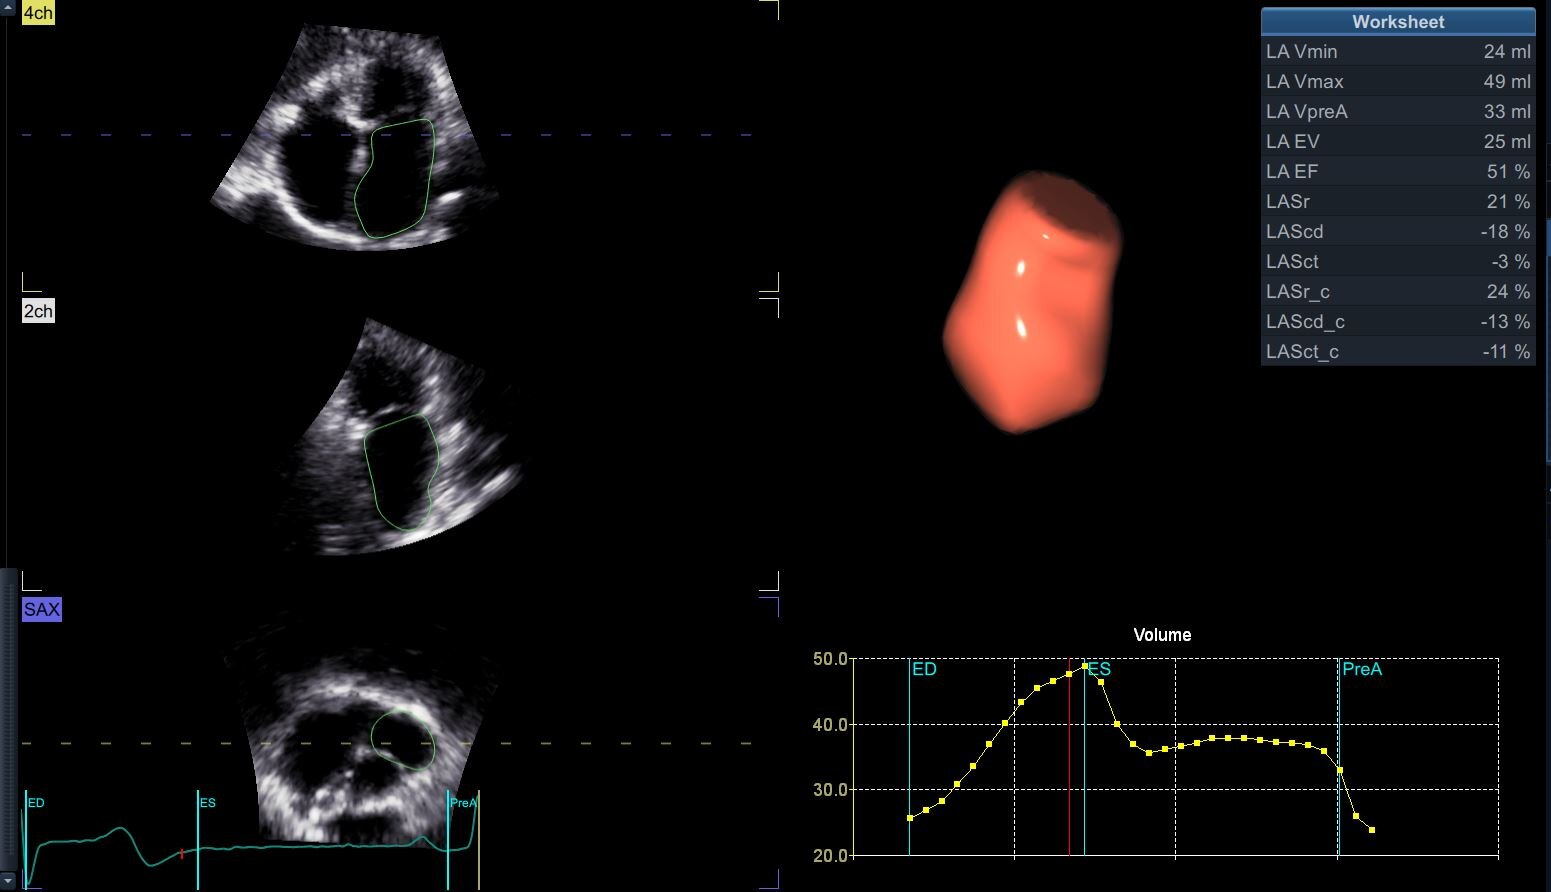

4D Auto LAQ*

Define the care path Quantification with Vivid E95 is all about helping providers evaluate problems and pursue the path forward. Count on a full suite of intuitive tools to make your work easy and efficient. Quickly, accurately and thoroughly quantify left and right ventricular wall motion and other key functions.